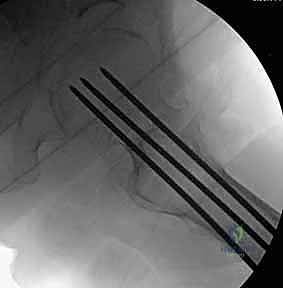

هي مسامير طبية متطورة مصنوعة من التيتانيوم (Titanium) أو الفولاذ المقاوم للصدأ (Stainless Steel). السمة المميزة لها هي وجود "تجويف" أو نفق يمتد عبر مركز المسمار بالكامل. هذا التصميم العبقري يسمح للجراح بإدخال سلك توجيهي رفيع (Guide Wire) أولاً في العظم لتحديد المسار الدقيق، ثم يتم تمرير المسمار المجوف فوق هذا السلك لينزلق مباشرة إلى المكان المحدد بدقة مليمترية.

لماذا نستخدم 3 مسامير؟ (هندسة المثلث المقلوب)

يعتمد الأستاذ الدكتور محمد هطيف على مبادئ الميكانيكا الحيوية (Biomechanics) في التثبيت. يتم عادةً إدخال ثلاثة مسامير متوازية في عنق الفخذ. لا يتم وضعها بشكل عشوائي، بل تُرتب في شكل مثلث مقلوب (Inverted Triangle):

1. التجهيز والتخدير (Preparation & Anesthesia)

يتم تخدير المريض (غالبًا تخدير نصفي/شوكي، أو تخدير عام حسب الحالة). يُوضع المريض على طاولة عمليات خاصة تُسمى "طاولة الشد العظمي" (Fracture Table). تتيح هذه الطاولة للدكتور هطيف تطبيق شد دقيق على الساق لرد الكسر إلى مكانه الطبيعي دون الحاجة لفتح الجلد.